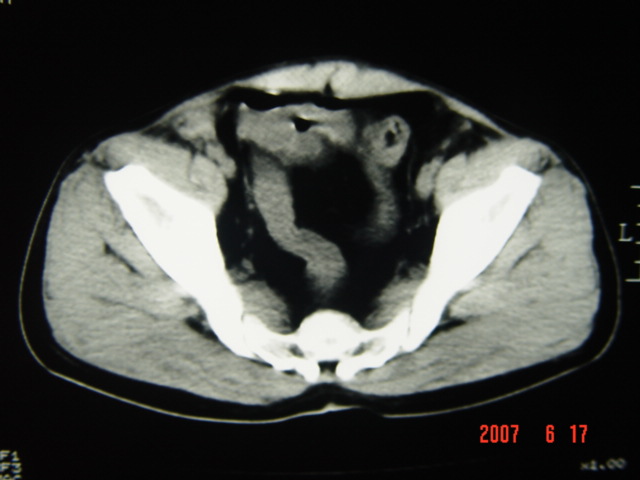

[br][br]以下是引用lkc8963在2007-6-17 13:32:00的发言:[br]完全支持邓主任意见:降/乙交界部占位性病变伴不全梗阻.做个增强或者be可能更好.